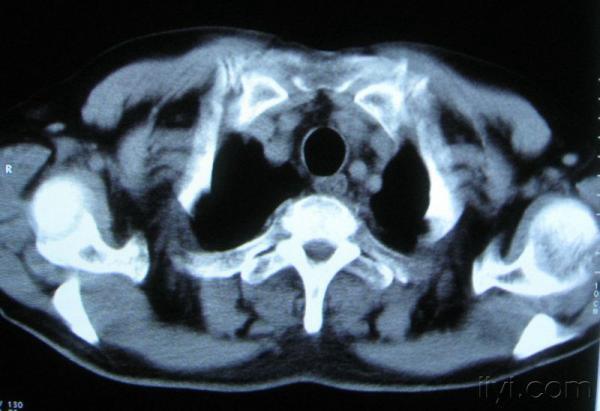

你指那个肯定是淋巴结,中央系坏死,这很常见,特别在双侧腹股沟会经常看到。这个双侧腋窝及纵隔见多发小淋巴结征。

根据位置考虑应该是淋巴结,密度不均,是因为肿大的淋巴结中心液化坏死